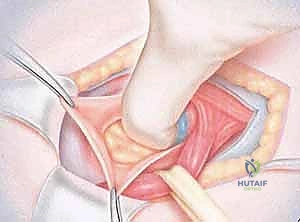

- استكشاف الأنسجة وتحرير الأعصاب: هذه خطوة حاسمة تتطلب مهارة جراحية فائقة (Micro-surgical skills). يتم فحص الجدار الخلفي للقناة الإربية بدقة لتحديد موقع التمزق والضعف. الأهم من ذلك، يقوم الدكتور هطيف بتحديد وتحرير الأعصاب الحسية (مثل العصب الحرقفي الإربي) التي قد تكون محاصرة أو مضغوطة بسبب الأنسجة المتمزقة، وهو ما يقضي على الألم المزمن فوراً.

- إعادة البناء وزرع الشبكة المزدوجة: يتم خياطة الأنسجة المتمزقة برفق، ثم يتم إدخال وتثبيت الشبكة المزدوجة. الجزء السفلي من الشبكة ينزلق تحت اللفافة المستعرضة (لدعم الجدار الخلفي من الداخل)، بينما يوضع الجزء العلوي فوقها، مع وجود موصل يربط بينهما. يتم تثبيت الشبكة بغرز دقيقة لضمان عدم تحركها.

- الإغلاق التجميلي: يتم إغلاق الشق الجراحي بغرز تجميلية تذوب من تلقاء نفسها، وتوضع ضمادة معقمة.